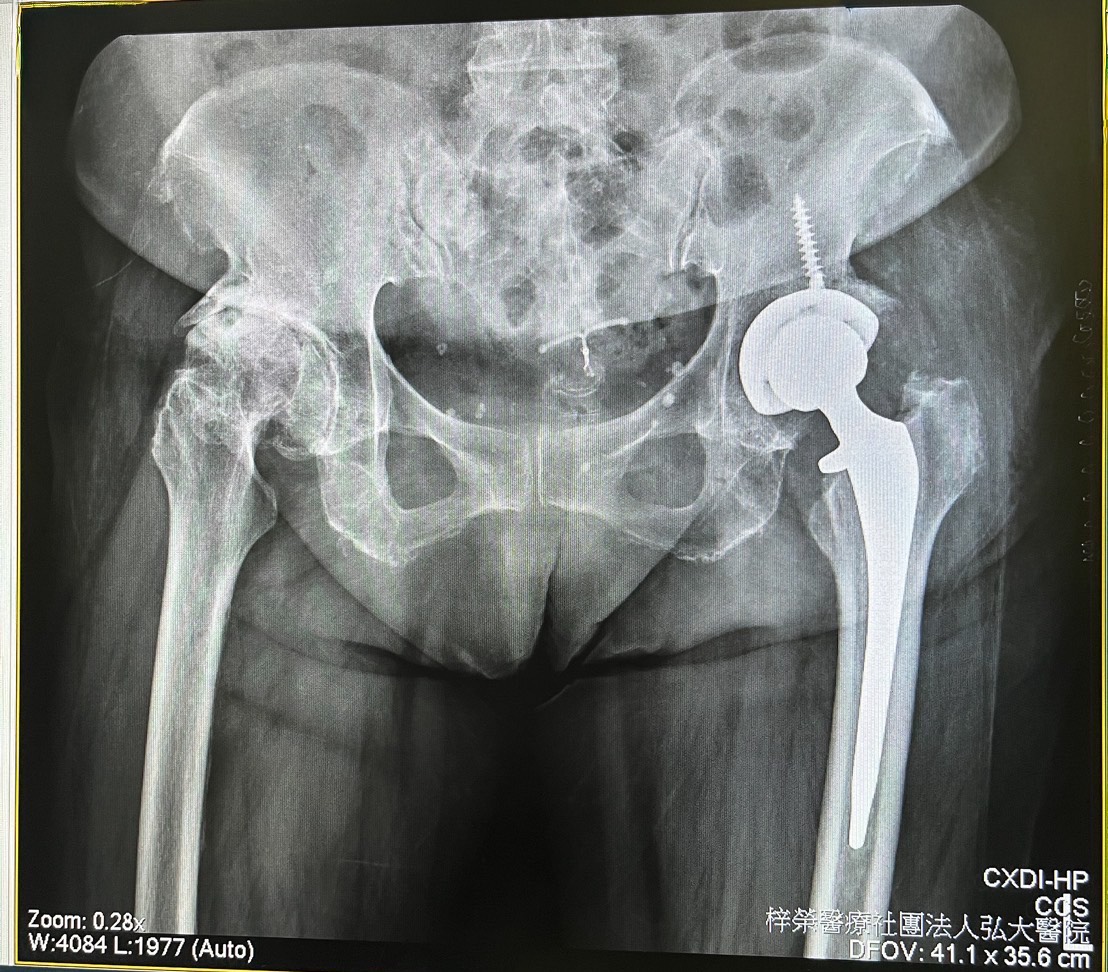

一名70多歲的女性患者,兩年前因為雙膝關節疼痛,於他院陸續接受人工膝關節置換手術。雖然術後症狀稍有改善,但她仍然感到步行困難,且疼痛逐漸加劇。經過原手術醫院多次追蹤檢查,認為置換後的人工膝關節並無異常,因而建議病人持續復健。然而,即使努力復健,病情依舊沒有改善。

圖1.  患者於他院置換的兩側人工膝估節